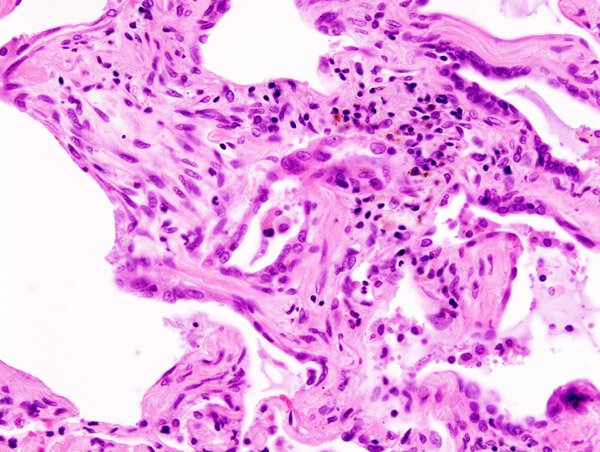

Interstitial Pneumonia

Interstitial pneumonia is also known as atypical pneumonia.

Diffuse interstitial infiltrates are the defining features of interstitial pneumonia.

Interstitial pneumonia presents with only a few minor upper respiratory symptoms (low fever, little sputum) which is an ‘atypical’ presentation.

Interstitial pneumonia is typically caused by bacteria or viruses.